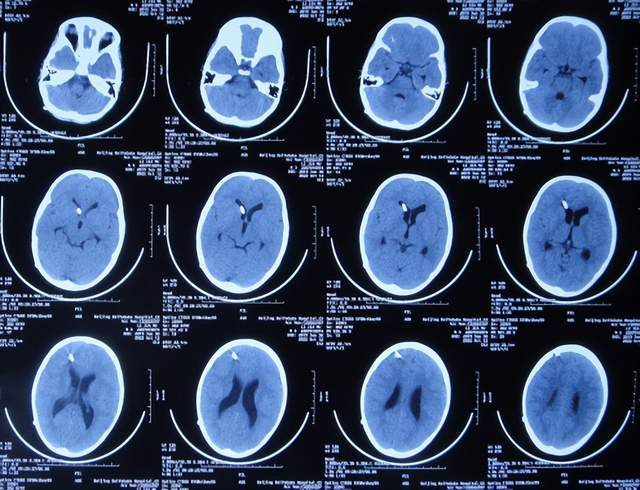

住院治疗7天即2022年5月18日,出现头痛,呕吐,体温再次升高为39.6度,心电图示室性心动过速,室早,考虑“心肌炎”,查头颅核磁(图-1)后并行腰穿见脑脊液呈金黄色,留取脑脊液送常规化验提示诊断为颅内感染,给予抗感染治疗。

图-1:2022年5月18日头颅核磁

第3家医院治疗16天即2022年6月9日,不但依然发热,而且查头颅CT示脑室稍扩张(图-3)。

图-3:2022年6月9日头颅核磁

但该院治疗12天即2022年6月29日,复查头颅核磁脑室扩张进一步加重(图-6)。

图-6:2022年6月29日头颅核磁

入院当天查头颅CT示脑室扩张(图-8)。

图-8:2022年7月1日入院时头颅CT

住院治疗18天即2022年7月18日,查头颅CT示脑室有缩小(图-12)。

图-12:2022年7月18日头颅CT

住院治疗63天即2022年9月1日,常规查头颅CT示脑室引流术后状态(图-15)。

图-15:2022年9月1日头颅CT

2022年10月12日(住院治疗104天),已夹闭脑室引流管3天,查头颅CT示脑室未见异常(图-17)。

图-17:2022年10月12日头颅CT

2022年10月25日(李小勇脑脊液科治疗117天),出院时:精神状态挺好,大小便正常,虽右腿走路稍差但走路速度变快,变稳(图-19);出院时头颅CT示未见异常(图-20)。

图-20:出院时头颅CT